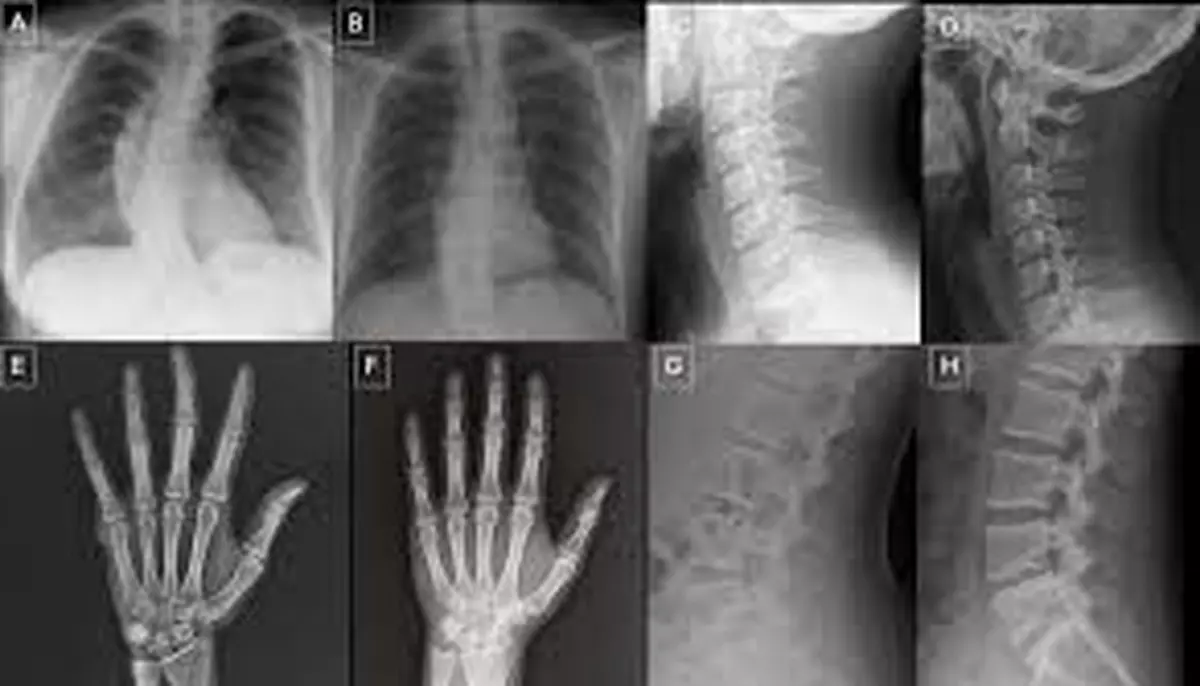

Primul set includea 77 de radiografii reale și 77 sintetice, generate de ChatGPT-4o, acoperind mai multe zone anatomice: piept, coloană vertebrală și extremități. Al doilea set era alcătuit exclusiv din radiografii toracice, jumătate autentice, jumătate produse de RoentGen, un model de difuzie generativă open-source dezvoltat de cercetătorii Stanford Medicine.

Cum arată o radiografie prea perfectă

Studiul a identificat și câteva trăsături comune ale imaginilor sintetice. Sunt indicii utile pentru viitoarele programe de formare. Liniile de fractură generate de AI tind să fie nenatural de netede, curate și uniforme. Sunt lipsite de neregularitățile biologice tipice traumatismelor reale. „Imaginile medicale deepfake arată adesea prea perfect”, a conchis dr. Tordjman.

Paradoxul este memorabil. Tocmai absența imperfecțiunii, a zgomotului imaginii, a asimetriei, a micilor anomalii care însoțesc orice corp real, poate trăda originea artificială a unei imagini.